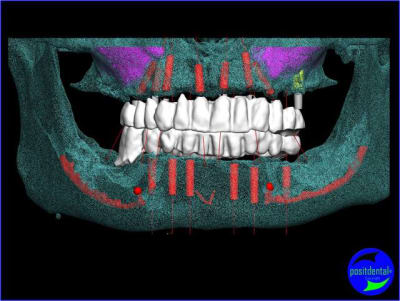

1er étape le wax-Up, dans ce cas clinique il est réalisé en 3D

guide de positionnement et intrado du bridge provisoire